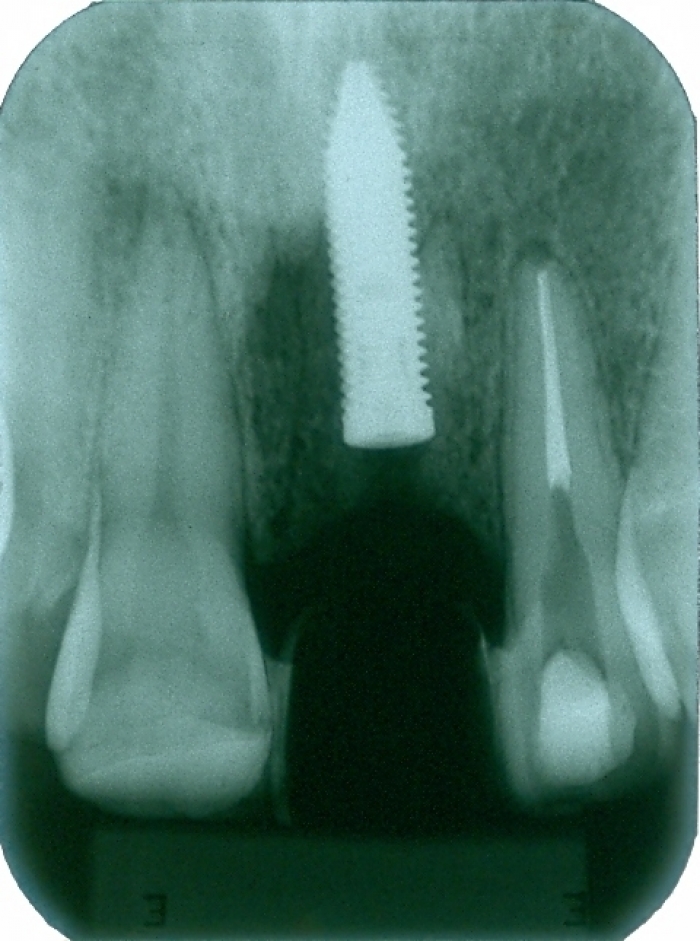

Raio X com prótese provisória fixa instalada

Raio X com dente de porcelana instalado